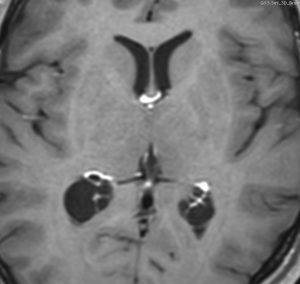

多くは側脳室の中にみつかります。丸いものや楕円形のものがあります。これも脳腫瘍と間違われることがあるのですが,脈絡叢にくっつく位置にあって,内部が髄液であることで区別できます。脳室内脈絡叢のう胞と脳室内くも膜のう胞は区別できませんが,両方ともほっておけばいいので心配ありません。

choroidplecyst側脳室三角部によくみられる両側性の脈絡叢のう胞です。成人女性にみられたものです。左右の大きさが違うこともありますし,脈絡叢がある部位ならどこでも発生するものです。脳室内くも膜のう胞と区別できないようなものもあります。